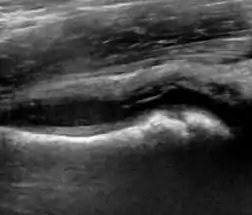

A step between the head and the physis can be detected in children with SCFE, while abnormalities in the femoral head contour may suggest the presence of LCPD. In both cases, radiographs are mandatory to confirm diagnosis and severity (Figure 12).[1]

Figure 12:

Joint effusion in transient synovitis of the hip.